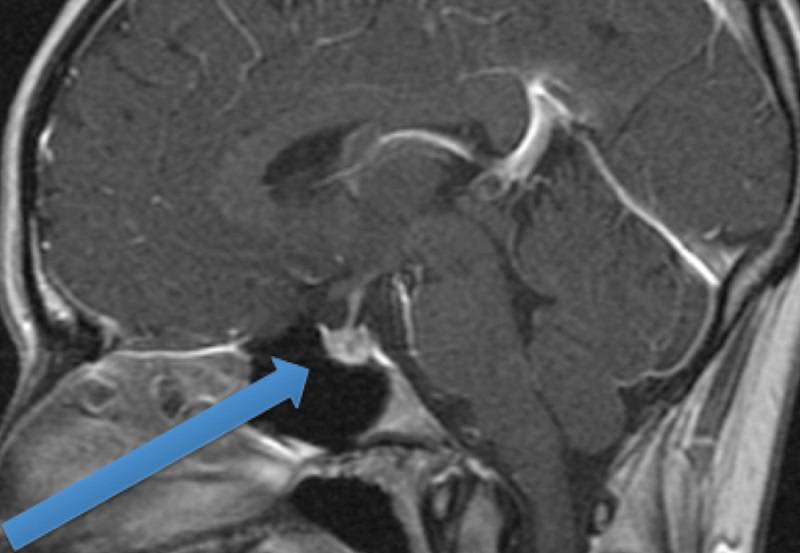

Meningioma

مننژیوم یک تومور است که از غشاهای مغز و نخاع (مننژ) فرد نشات میگیرد. اکثر مننژیوم ها در مراحل اولیه که اندازه تومور کوچک است و اثر فشاری روی بافتهای اطراف ندارند، غیرقابل تشخیص هستند.

Craniopharyngiomas

رشد این تومور در اطراف غده هیپوفیز شروع می شود. همانطور که به آرامی رشد می کند، می تواند بر غده هیپوفیز و دیگر ساختارهای مغز تاثیر بگذارد.